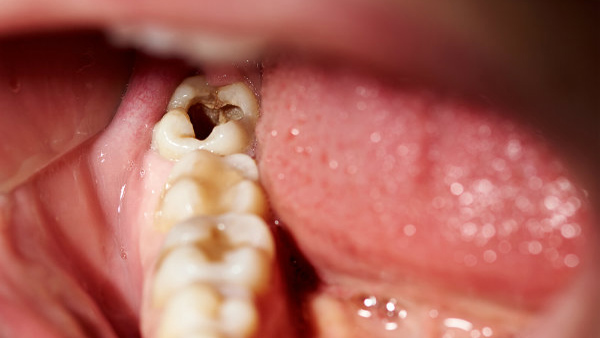

ആദ്യം ഒരു കറുത്ത പുള്ളി, പതിയെ പതിയെ ദ്വാരം: ഇതെല്ലാം കഴിക്കുന്നവര് അറിഞ്ഞിരിക്കണം

പല്ലിന്റെ ആരോഗ്യം എപ്പോഴും ഒരു വെല്ലുവിളി തന്നെയാണ്. അതില് പ്രധാനമായും സംഭവിക്കുന്ന പ്രതിസന്ധികള് എന്ന് പറയുന്നത് എപ്പോഴും പല്ലിലെ പോടും, വായ്നാറ്റവും മോണരോഗവും പോലുള്ളതാണ്. എന്നാല് ഈ പ്രശ്നം നമ്മള് അല്പമൊന്ന് ശ്രദ്ധിച്ചാല് പരിഹരിക്കാന് സാധിക്കുന്നതും ആണ് എന്നതാണ് സത്യം. തിളക്കമുള്ള പുഞ്ചിരിക്കും പാല്നിറമുള്ള പല്ലിനും വേണ്ടി ചില കാര്യങ്ങള് ശ്രദ്ധിക്കാവുന്നതാണ്. പലപ്പോഴും നല്ല ദന്താരോഗ്യം നിലനിര്ത്തുക എന്നത് അല്പം കഷ്ടപ്പാടുള്ള പണി തന്നെയാണ്. എപ്പോഴും ദന്താരോഗ്യത്തെ സംരക്ഷിക്കുന്നതിന് വേണ്ടി ശ്രമിക്കുമ്പോള് അറിഞ്ഞിരിക്കേണ്ട ചിലതുണ്ട്.

ഒഴിവാക്കേണ്ട ഭക്ഷണങ്ങള് തന്നെയാണ് അതില് ആദ്യം വരുന്നത്. പല്ലിലെ പോടുകള്ക്ക് കാരണമാകുന്നതും പല്ല് ക്ഷയിക്കാന് കാരണമാകുന്നതും എല്ലാം ഇത്തരത്തില് ചില ഭക്ഷണങ്ങള് തന്നെയാണ്. പല്ല് ക്ഷയിക്കാന് കാരണമാകുന്ന ആസിഡുകള് ഉത്പാദിപ്പിക്കപ്പെടുമ്പോഴാണ് ഇത്തരത്തില് സംഭവിക്കുന്നത്. ഇത് പല്ലിലെ ഇനാമലിനെ പ്രശ്നത്തിലേക്ക് എത്തിക്കുന്നു. ഇത് വഴി പല്ലില് പോടുകളും ഉണ്ടാവുന്നു. പല്ലിനെ പോടില് നിന്ന് സംരക്ഷിക്കുന്ന ചില ഭക്ഷണങ്ങള് ഉണ്ട്. അവ എന്തൊക്കെയെന്ന് നോക്കാം.

എപ്പോഴും ആദ്യം ശ്രദ്ധിക്കേണ്ടത് പഞ്ചസാര അടങ്ങിയ മിഠായികളും ലഘുഭക്ഷണങ്ങളും ഒഴിവാക്കുക എന്നതാണ്. ഇത് പല്ലുകള് ക്ഷയിക്കുന്നതിനും പല്ലില് പോടുകള് വലുതാവുന്നതിനും കാരണമാകുന്നു. ഇത്തരം മധുരപലഹാരങ്ങളിലെ പഞ്ചസാര പല്ലില് ഒട്ടിപ്പിടിക്കുകയും പറ്റിപ്പിടിച്ചിരിക്കുകയും ചെയ്യുന്നു. ഇത് പല്ലിലെ ഇനാമലിനെ നശിപ്പിക്കുന്ന തരത്തിലുള്ള ആസിഡുകള് ഉത്പാദിപ്പിക്കുന്നു. അതുകൊണ്ട് തന്നെ പല്ലില് പതിയെ പതിയെ കറുത്ത കുത്തുകളും അത് പിന്നീട് പോട് പരുവത്തിലേക്ക് മാറുകയും ചെയ്യുന്നു.